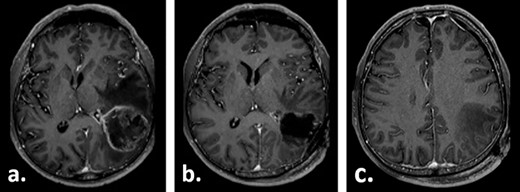

A 67-year-old male patient presented at a local hospital with progressive fatigue, memory and concentration loss, right-sided neglect and weakness as well as gait disturbance. A cerebral MRI scan depicted an inhomogeneous contrast-enhancing, left temporo–parieto–occipital intracerebral tumour invading the trigonum of the left lateral ventricle. The tumour was resected subtotally under 5-ALA fluorescence with a small remnant infiltrating the trigonum of the left lateral ventricle, which was opened intraoperatively (Fig. 1). Histologically, glioblastoma multiforme, WHO IV°, was diagnosed. No molecular analysis was performed.

Gadolinium-enhanced T1-weighted axial MRI of the patient preoperatively (a) and 1 day after the tumour resection (b, c).